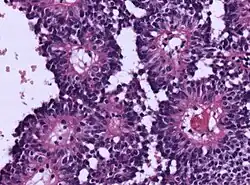

Das Astroblastom ist ein sehr seltener, bösartiger, vom Neuroepithel ausgehender Hirntumor und wird zu den Gliomen gerechnet. Es kommt meist bei Kindern und Jugendlichen vor.[1][2][3]

Es können niedrigmaligne Formen mit besserer Zelldifferenzierung und hochmaligne Formen mit anaplastischen Kernveränderungen, erhöhtem Mitoseindex, Nekrosen und Gefäßproliferation unterschieden werden.[1]